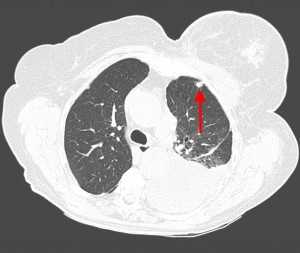

Контактные метастазы представлены мягкотканным объемным образованием, прорастающим из сопредельного органа. Это может быть пищевод, трахея, гортань, реже опухоль исходит из плевры (мезотелиома), диафрагмы, ребер, позвонков.

Пример контактного распространения опухоли: мезотелиома плевры, прорастающая в верхнюю легочную долю и грудную стенку. Спиральная компьютерная томография (МСКТ).